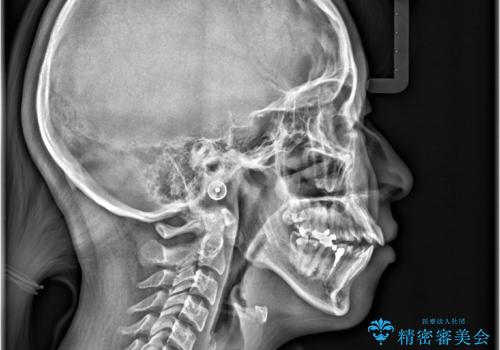

- 開咬と歯のデコボコ(叢生)、八重歯を主訴にご来院された患者様です。

矯正の精密検査の結果、上顎左右4番および下顎左右5番の計4本を抜歯し、ワイヤー矯正(クリア装置)にて治療を行いました。